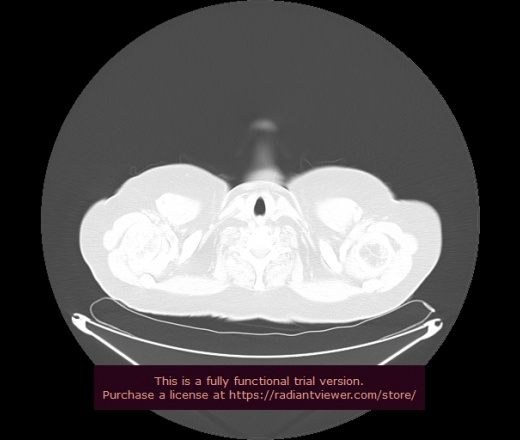

Уважаемые коллеги, если имеется интерес, сможете ли Вы спрогнозировать дальнейшее +-одинаковое течение процесса у 4 данных разных пациентов? Зацепиться где-то можно очень просто, где-то нельзя.